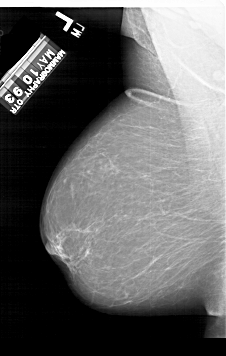

A_1115_1.LEFT_MLO

LEFT_MLO LINES 6751 PIXELS_PER_LINE 4291 BITS_PER_PIXEL 12 RESOLUTION 43.5 NON_OVERLAY

RIGHT_MLO LINES 6646 PIXELS_PER_LINE 4126 BITS_PER_PIXEL 12 RESOLUTION 43.5 OVERLAY

FILE: A_1115_1.RIGHT_MLO.OVERLAY

LESION_TYPE CALCIFICATION TYPE PLEOMORPHIC DISTRIBUTION SEGMENTAL

ASSESSMENT 4

SUBTLETY 4

PATHOLOGY MALIGNANT